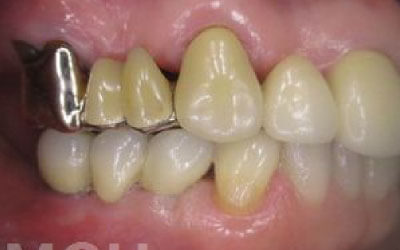

ブリッジとインプラントでは、周りの歯の寿命に大きな違いがあります。ブリッジは支えとなる歯を健康でもかなり削らなければならず、さらに噛む力が約1.5倍かかるため、その歯の寿命が短くなってしまいます。実際のデータでは、ブリッジの支えとなった歯の68%が10年以内に抜歯に至っています。

ブリッジ治療の場合も、失った歯にかかっていた力を前後の歯が支えるため、結果として残っている歯には、通常の1.5〜2倍ほどの負荷がかかってしまいます。

ブリッジなどの治療では、前後の歯を大きく削らなければならず、場合によっては虫歯でなくても神経を抜くことがあります。神経を抜いて被せ物をすると、その歯は一気に寿命の終わりに近づいてしまうのです。

残っている歯にとって、ブリッジ治療は非常にもったいない方法です。

その理由は、ブリッジを作るために前後の歯を大きく削らなければならないからです。

場合によっては、神経を取る必要があることもあります。

これだけ歯にダメージを与えるため、その歯の寿命が大きく縮むことになります。

最も大きな違いは、前後の歯の寿命に影響を与えることです。

ブリッジでは、抜けた歯の前後の歯を大きな虫歯と同じくらいまで削らなければならず、

また、抜けた歯の代わりに前後の歯がその力を支えるため、常に1.5倍の負荷がかかります。

1)ブリッジ

2)歯を大きく削る+支えの歯に1.5倍の力がかかる

3)前後の歯の寿命が著しく減る

ブリッジの支えの歯は、データでは10年以内に68%が抜歯になります。